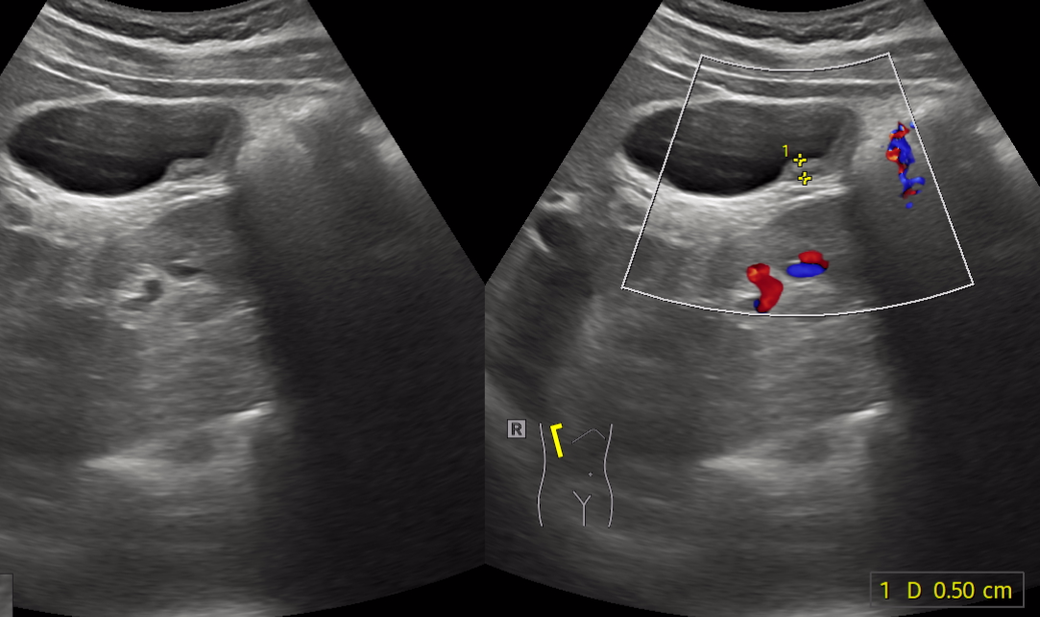

만 나이 25 남자입니다. 담낭암일 수 도 있나요? 가끔 과식할때 소화불량이 있어 우연치 않게 건강검진하다가 현재 초음파검사상 담낭벽비후 진단 받았고 ct결과 기다리는중입니다.

• 2번 째 사진